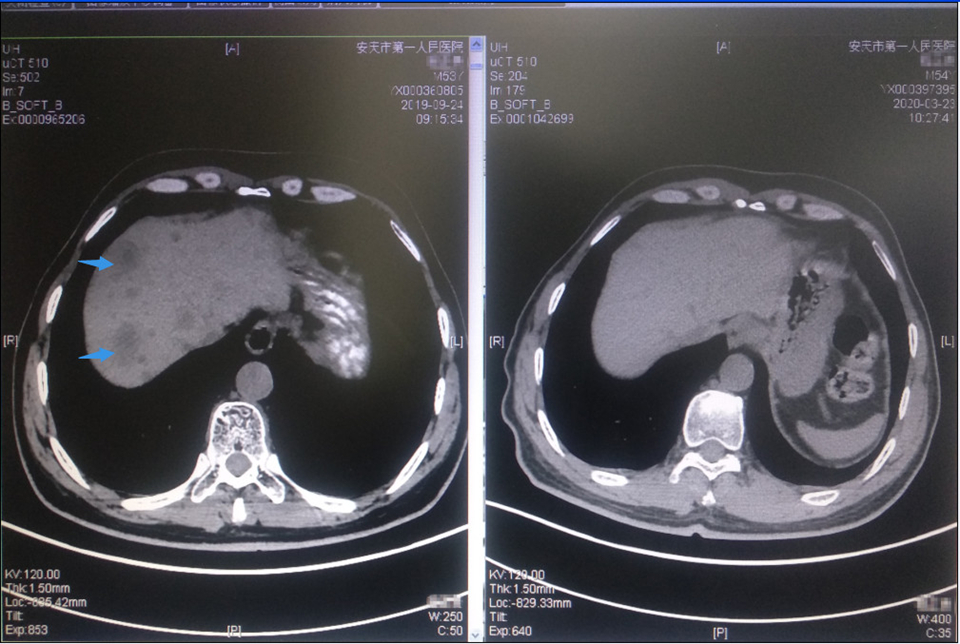

患者程XX,男,54岁。2018年11月,因“渐进性左侧腰痛加重2月”就诊,CT提示左侧腹膜后、左侧肾实质及肾门多发占位。住院行“左肾根治性切除+淋巴结清扫术”,术后病理:肾脏小细胞神经内分泌癌,肿块直径为9cm,癌组织侵犯肾盂、肾窦及肾周脂肪组织,脉管、神经见癌组织侵犯。肾门周围融合性淋巴结见癌转移,腹主动脉旁纤维组织癌浸润。术后一月就诊于我科,发现已出现锁骨上淋巴结转移。在给予三周期EP方案化疗后,肿瘤退缩不明显,并于2019年4月出现颅骨转移。我科给以颅骨局部放疗同时更换二线化疗方案为“替莫唑胺+卡培他滨”,颅骨局部转移灶控制,但仅仅过了两月(2019年6月),又出现原左肾手术区肿瘤复发,腹膜后多发淋巴结转移和多发椎骨转移。此时患者状况已经相对较差,对于二线化疗失败后的神经内分泌癌,国际上也没有肯定的治疗方案,国内仅少数文献报道抗血管生成靶向治疗可能有效,且有效率很低。为减轻患者局部复发病灶局部症状,我科再次针对于腹腔内复发病灶和骨转移灶姑息放疗并同时试用阿帕替尼抗血管生成治疗。虽然经过放疗,复发病灶病灶得以控制,但仅过一月后,患者就又再度出现了肝转移。这似乎说明,抗血管生成治疗对控制转移也无效,系统性治疗已到了无药可用的山穷水尽地步。此时,科室对于该患者的下一步处理,进行了科内讨论。最终,在基于对此类肿瘤病理学的深入研究,神经内分泌癌表现为较多淋巴细胞浸润和PD-L1表达,提示这类肿瘤可能从PD-1单抗治疗中获益。在参考其他肿瘤免疫治疗的成功经验后,同时个体化兼顾到患者当时身体状况难以耐受化疗,2019年8月份我科制定了下一步的治疗方案,继续保留副作用较小的阿帕替尼同时联合免疫检查点抑制剂特瑞普利单抗(PD-1单抗)治疗。仅仅给予了3周期的免疫联合抗血管靶向生成治疗(后因经济条件未继续治疗),患者肿瘤病灶几乎完全缓解,并持续起效。2020年3月,患者来我科复查,身体状况恢复正常, CT提示肝脏转移瘤完全消失,其他部位转移灶也继续保持接近完全缓解状态。

(免疫联合抗血管生成靶向后:箭头示多发肝转移灶消失)